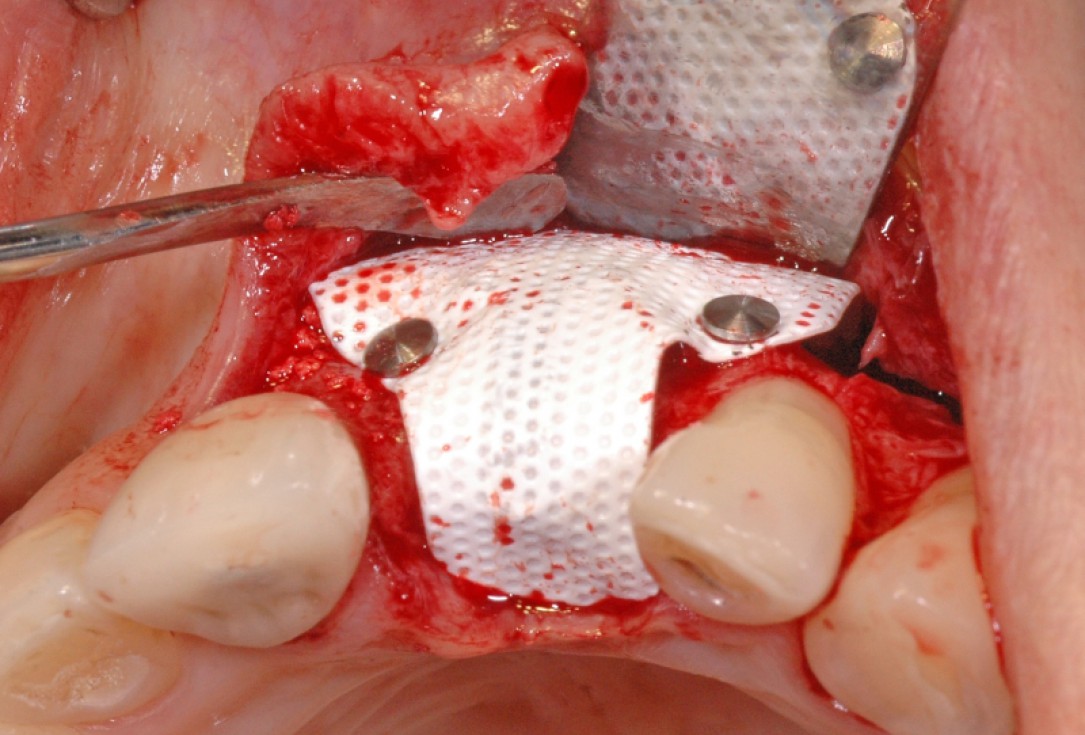

6/18 - Augmentation with maxresorb® and covering with a non-resorbable PTFE membraneGBR together with soft tissue augmentation with mucoderm® and maxresorb® - Dr. S. Scherg

7/18 - Fixation of the membrane with titanitum pinsGBR together with soft tissue augmentation with mucoderm® and maxresorb® - Dr. S. Scherg